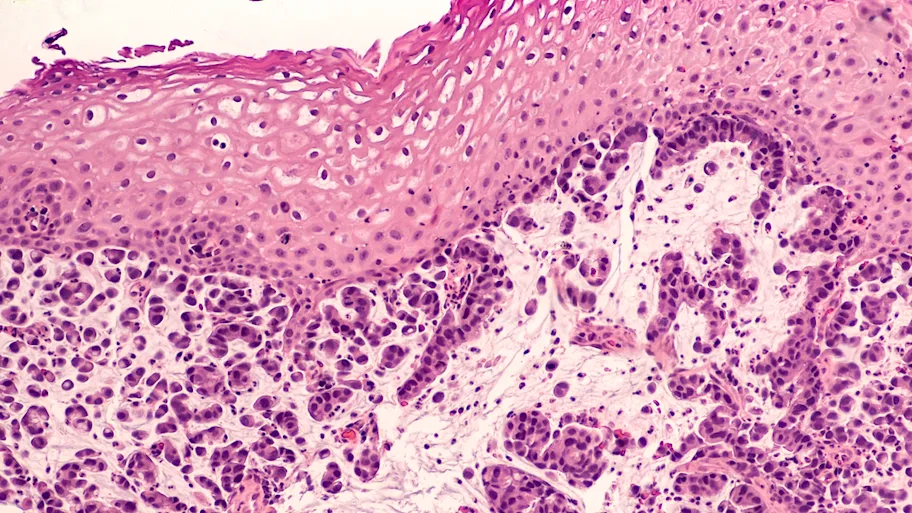

Further studies are needed to assess the anti-cancer potential of a high-salt diet, as high salt intake is also a suspected risk factor for gastric cancer. Image: Shutterstock.

A high salt diet inhibited tumor growth in two independent mouse models

An international research team led by Prof. Kleinewietfeld that included Prof. Sven Brandau (University of Duisburg-Essen, Germany), Dr. Thomas Kammertöns (Charite & MDC-Berlin, Germany) and Prof. Jo Van Ginderachter (VIB-VUB) have now investigated the impact of high salt intake on tumor growth in mice. They found that a high salt diet inhibited tumor growth in two independent mouse models. The research team further found that this effect seemed to be related to a change in the functions of certain immune cells, so called myeloid-derived suppressor cells (MDSCs). MDSCs are believed to hinder other immune cells to efficiently attack and eliminate tumor cells.